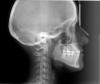

salofa Опубликовано 8 ноября, 2007 Поделиться Опубликовано 8 ноября, 2007 Добрый день!Собираюсь ставить брекеты.Сделаны 2 снимка: ОПТГ и ТРГ в боковой проекции.О чем они говорят? Ссылка на комментарий

Премоляр Опубликовано 8 ноября, 2007 Поделиться Опубликовано 8 ноября, 2007 если я скажу вам что имеет место соотношение моляров справа по 2 классу,слева по 3 классу,обратная резцовая окклюзия 21,22,тесное положение зубов на вер. и ниж. челюстях..Это что то изменит?Или вместо брекетов у вас есть какая то другая альтернатива??? Ваша фраза "...патология прикуса по фото.." напоминает мне объявление в газете-"сниму порчу и сглаз по фото.Результат гарантирую" Ссылка на комментарий